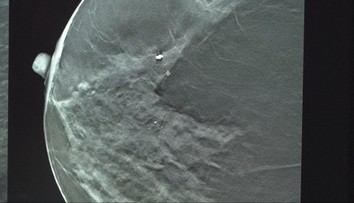

"Vďaka opakovanému vnútromaternicovému zákroku v druhom trimestri s laserovým cieleným uzáverom prívodných ciev nádoru sa zmenšil jeho objem o polovicu," znie v stanovisku Centra fetálnej medicíny ÚPMD. Išlo o vôbec prvú vnútromaternicovú operáciu tohto typu v Česku a na Slovensku.

Lekári sa podelili o video tohto obrieho nádoru. Ten aj po zmenšení vážil desivých 1,2 kilogramu.

Táto veľkosť ale už, našťastie, pre vyvíjajúci sa plod nepredstavovala život ohrozujúce rozmery. Celý prípad skončil úspešne, keďže bábätko je prakticky bez problémov.